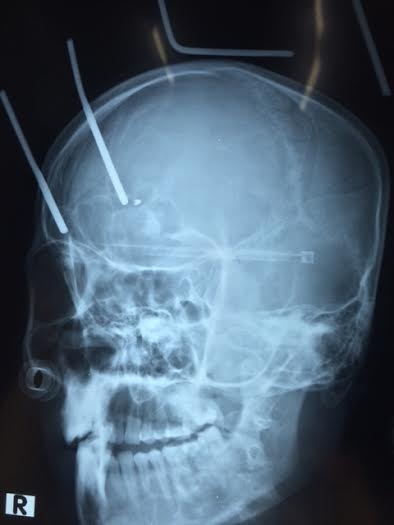

| Bệnh Nhân Thái Văn Tú được cứu sống thần kỳ khi bị hai thanh sắt đâm xuyên từ đỉnh đầu vào não sâu hơn 9 cm. |

Chiếc cào sắt cắm thẳng vào đầu, hai đinh sắt xuyên từ đỉnh đầu vào não anh Tú tới 9 cm. Những người có mặt tại hiện trường lập tức đưa anh Tú đi cấp cứu tại bệnh viện đa khoa Hà Tĩnh. Nhưng do vết thương quá nặng anh Tú được người nhà đưa ra bệnh viện ở Hà Nội để tiếp tục cứu chữa.

| Hình ảnh chụp Xquang cho thấy hai thanh sắt đâm sâu vào não bộ của anh Tú. |

Ông Hoàng Hoa Thám, Trưởng khoa thần kinh cột sống, Bệnh viện Đa khoa tỉnh Nghệ An, cho biết: “Ngay sau khi chẩn đoán, khám cho bệnh nhân chúng tôi đã tiến hành phẫu thuật với ê kíp gồm 4 người. Vì hai thanh sắt cắm sâu vào não bộ nên quá trình tiến hành phẫu thuật gặp rất nhiều khó khăn. Hơn 2 giờ sau chúng tôi mới lấy được hai thanh sắt ra khỏi đầu nạn nhân. Đây là một ca phẫu thuật vô cùng phức tạp mà lần đầu tiên bệnh viện thực hiện và kết quả thành công ngoài mong đợi.